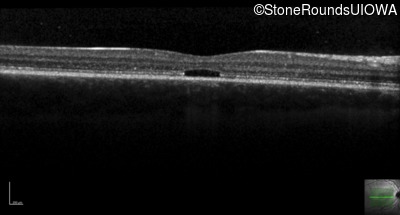

Optical Coherence Tomography - Right - 20/160 +2

Exemplar / OCT Stack

OCT Stack